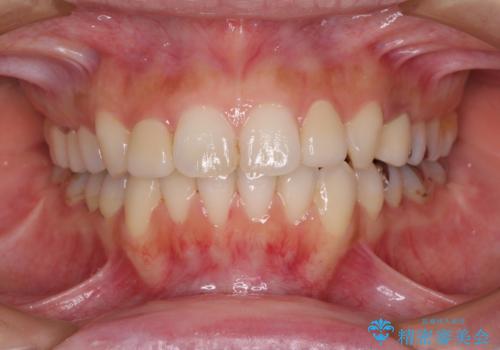

複数歯の補綴治療を行う場合、仮歯やセラミッククラウンを装着する度に保定装置を作り替える必要があり、その度に後戻りを起こす可能性が高くなります。

インビザラインであれば、矯正治療後半で補綴治療を行い、その後矯正治療を継続することでスムーズに治療を終えることができます。